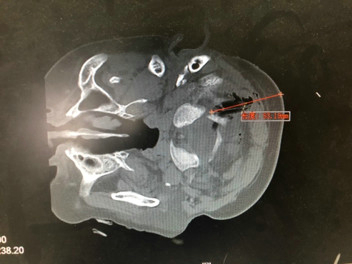

急查头部CT显示这段树枝直接嵌入在枕颈交界区,毗邻最重要的结构——颈髓和椎动脉旁。通常这个位置是手术风险极高的区域,稍有不慎动脉出血可能是致命性的,颈髓损伤也可能会出现终身瘫痪残疾,凶险程度可见一斑。

CT显示树枝位于颈枕交界区,寰椎后弓有骨折,毗邻椎动脉管